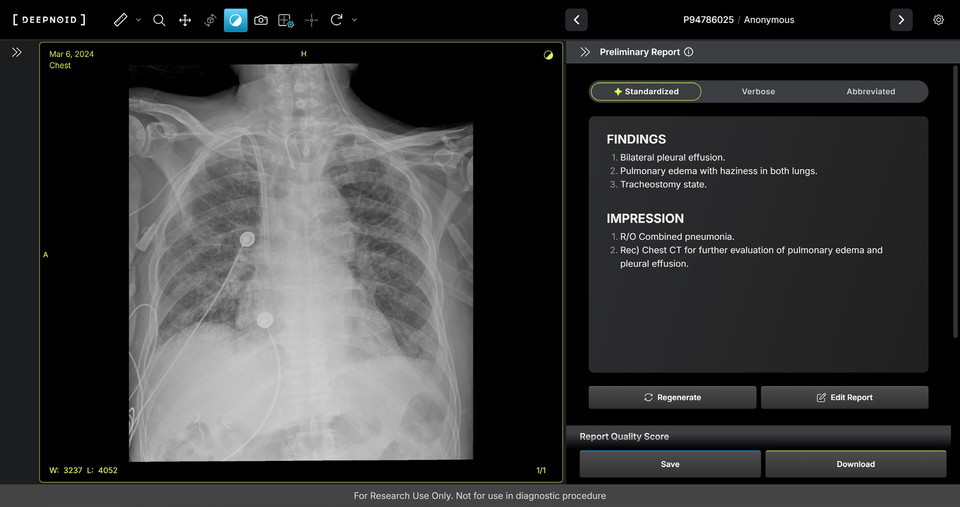

M4CXR은 흉부 X-ray 영상에서 41종의 병변을 판독해 수초 만에 일관성 있고 신뢰성 높은 판독소견서 초안을 작성한다고 한다.

이는 흉부 X-ray 영상과 대응되는 1000만 건 이상의 판독소견서 데이터를 학습해 구현된 기술로 특히 응급상황에서 의료진이 즉시 예비 판독 결과를 받을 수 있어 중요한 임상 결정과 환자 진료에 더욱 집중할 수 있도록 지원하며 영상의학과 전문의의 판독을 보조한다는 소개다.